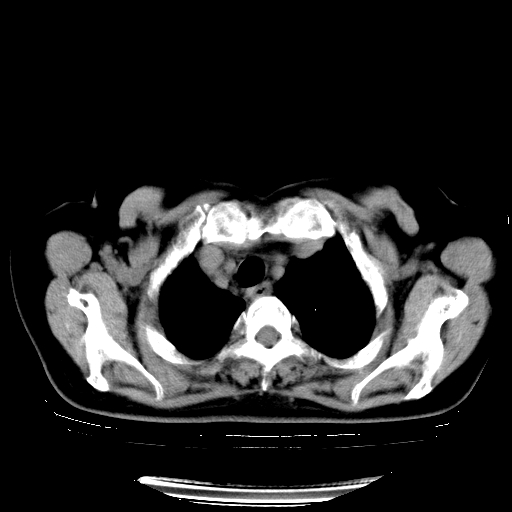

以下是引用zhangzhongshou在2008-3-22 12:52:00的发言:[br]1、右侧液气胸。[br]2、腹水。建议进一步检查。

以下是引用鲁巨ct在2008-3-22 14:10:00的发言:[br]1、右侧液气胸,右中下叶节段性不张。[br]2、腹水,建议上腹部ct检查

以下是引用zjzjr在2008-3-22 17:19:00的发言:[br]1、右侧液气胸,右下叶节段性不张。[br]2、腹水,建议上腹部ct检查